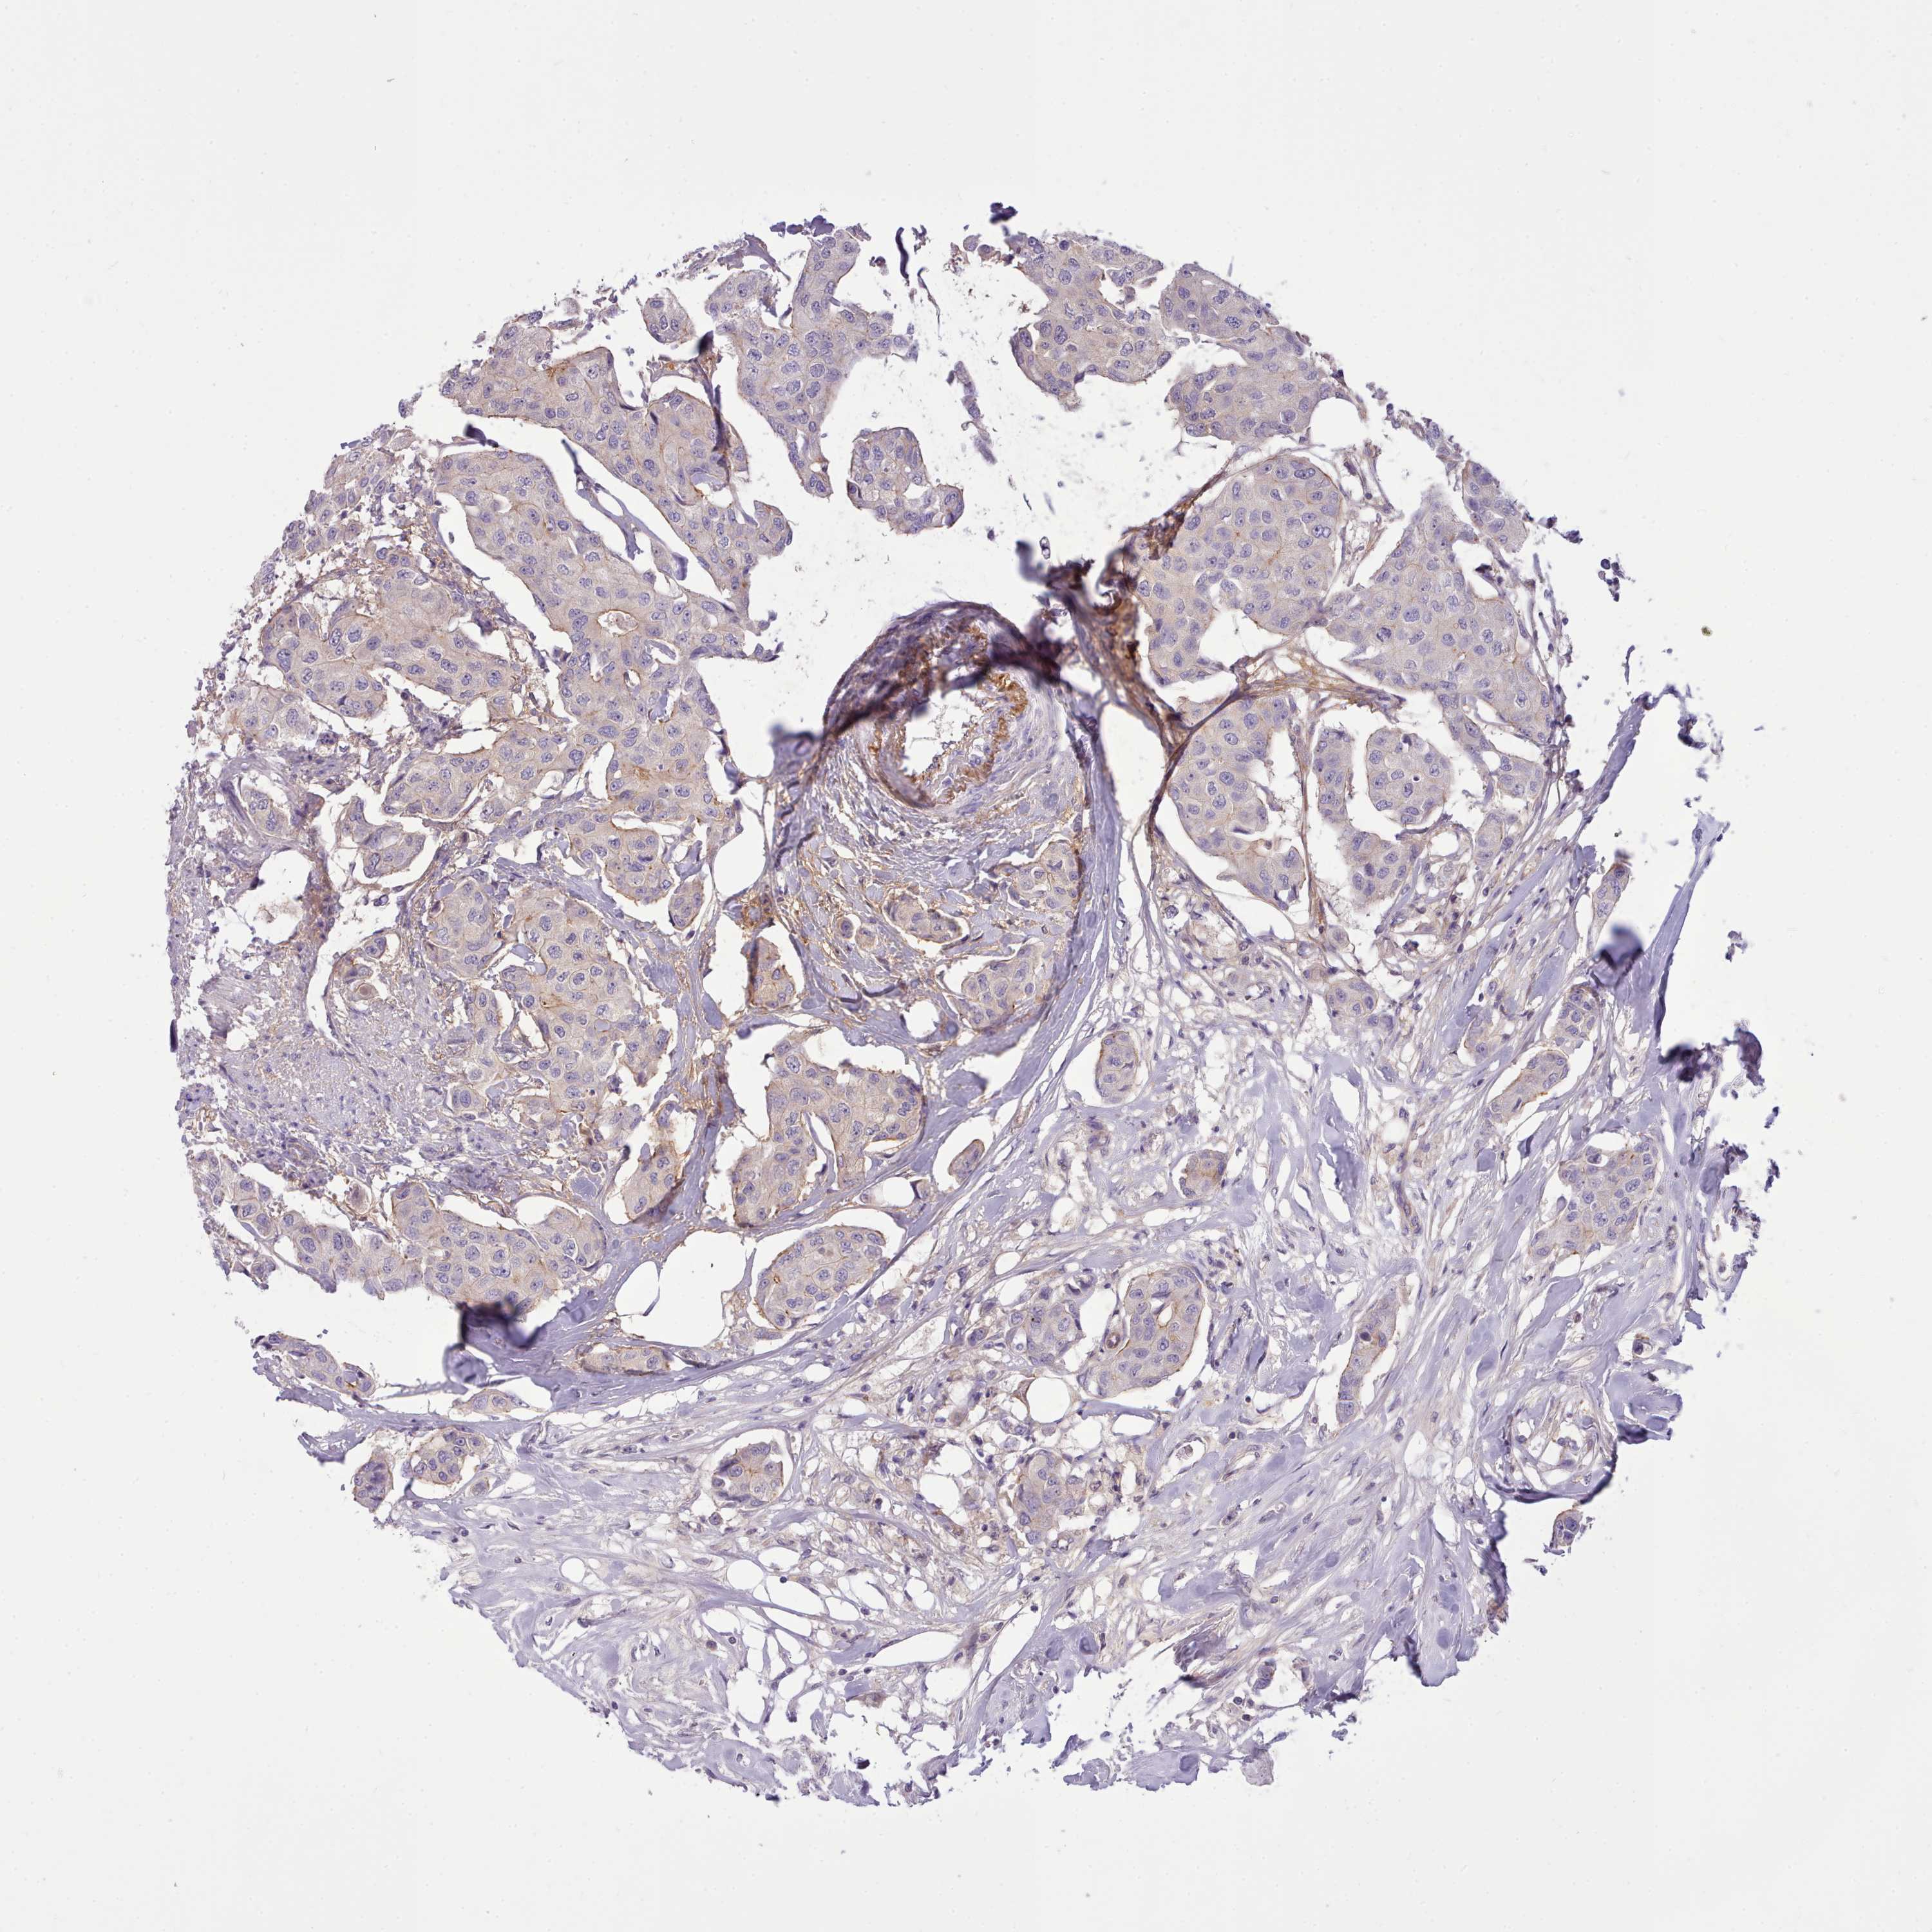

CANCER BREAST CANCER Show tissue menu

BRCA TCGA BRCA VALIDATION PROTEIN EXPRESSION

ANTIBODIES

AND

VALIDATION